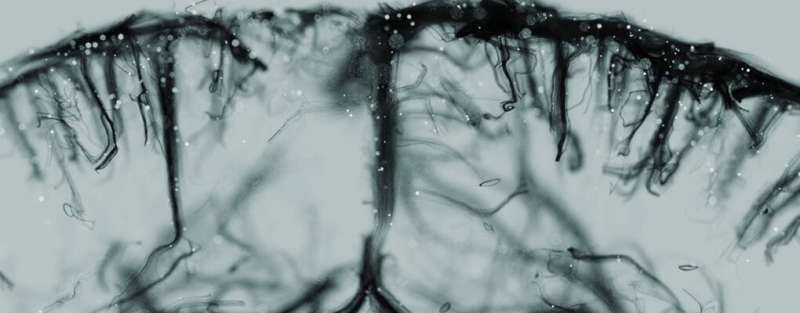

这项研究主要使用来自志愿者的细胞在体外培养人类皮肤以进行感染。鼠类模型也被用来研究皮肤如何与免疫细胞相互作用。